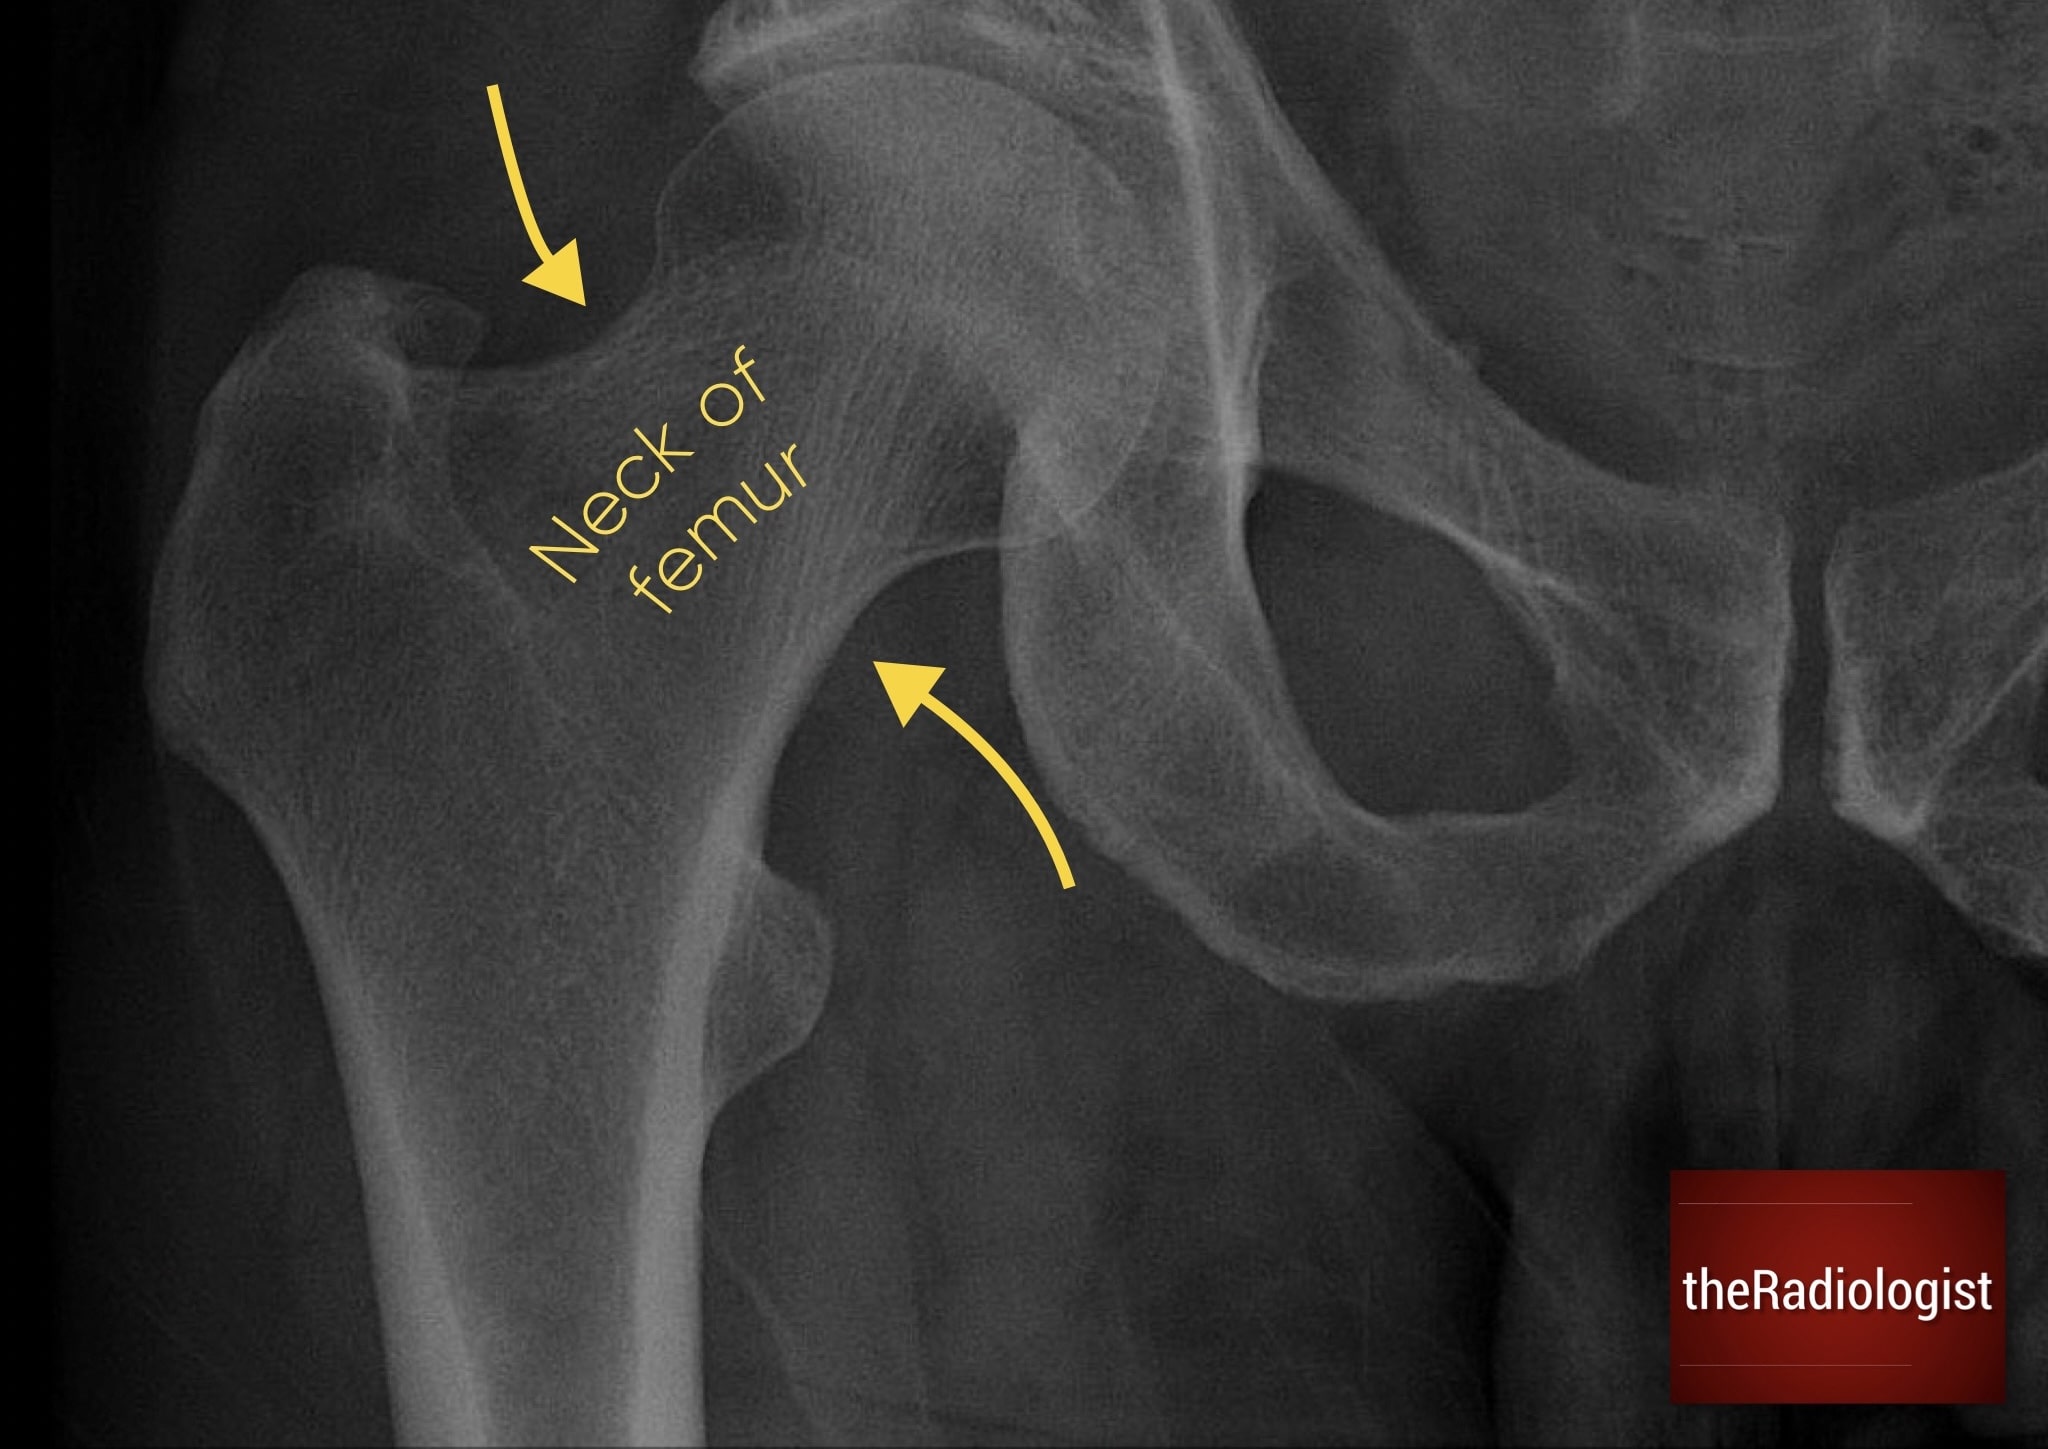

N: Neck of femur

Examine both femoral necks carefully. Fractures here can be subtle and seen only as a faint lucent line or the internal trabeculae being slightly angled. The line can be sclerotic if there is overlapping bone and an impacted fracture.

Use Shenton’s line, the smooth arc formed by the inferior border of the superior pubic ramus and the inferomedial femoral neck (see the hip X-Ray anatomy diagram above). Any disruption of this in the context of trauma could represent a neck of femur fracture. Also inspect the greater and lesser trochanters for cortical breaks or avulsions.

Annotated image of a lateral hip X-Ray.

1. Femoral neck

The femoral neck should be your first focus. Look carefully for a lucent line or cortical disruption, both of which may indicate a fracture. Be aware, though, that impacted fractures can appear as a sclerotic band rather than lucent, as overlapping bones create increased density.

2. Femoral head and acetabulum

Next, assess the articulation between the femoral head and acetabulum and make sure there is no subluxation or dislocation. Trace the outline of the acetabulum wherever it is visible and check for breaks in the cortex.

3. Trochanters

Finally, move to the greater and lesser trochanters. These should be followed carefully. Any discontinuity, sharp angulation, or small separate fragment of bone may represent a displaced fracture or avulsion fracture.